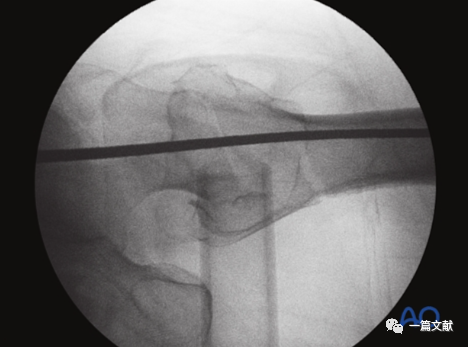

侧位片主要用来判断骨折复位情况及前倾角。但是,侧位片不是判断内固定位置的最佳选择,如下图:

同一患者的侧位像与轴位像的内固定透视图像如下图: